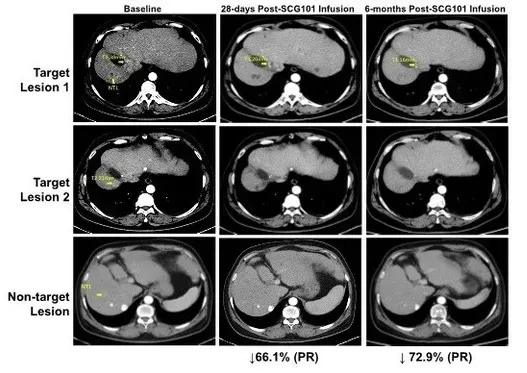

2023年国际细胞与基因治疗大会(ISCT)上,公布了一例SCG101治疗HBV相关肝细胞癌的惊艳案例。该患者经单剂SCG101治疗后达到部分缓解(PR),肿瘤病灶与HBV感染均实现显著改善。

1、肿瘤病灶显著缩小:治疗后第28天,患者肿瘤靶病灶较基线缩小66%;治疗第4个月时,肿瘤病灶进一步缩小至较基线下降74.5%,同时另有1处病灶完全消失;截至数据统计时,患者的无进展生存期已超过6.9个月。

▲图源“CISION”,版权归原作者所有,如无意中侵犯了知识产权,请联系我们删除